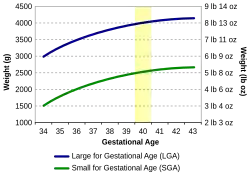

To have a good estimate of birth weight, ultrasonography or ultrasound during pregnancy and the date of last menstrual period are needed.[27] Measured values from ultrasonography are compared with the growth chart to estimate fetal weight.[28]

Crown-rump length can be used as the best ultrasonographic measurement for correct diagnosis of gestational age during the first trimester.[27] This correlation between crown-rump length and gestational age would be most effectively shown when no growth defects are observed in the first trimester.[27] If growth defects were observed in the first trimester, then the measurement of the date of last menstrual period becomes quite important since the crown-heel length has become less of a reliable indicator of gestational age.[27]

After the 20th week of pregnancy, the mother would need to visit the doctor for the measurement of fundal height, which is the length from the top portion of the uterus to the pubic bone.[28] The length measured in centimeters should correspond to the number of weeks that the mother has been pregnant.[28] If the measured number is higher or lower than 2 centimeters, further tests using ultrasound would be needed to check the results.[28] Another way to estimate fetal size is to look at the mother's weight gain.[28] How much weight the mother gains can be used to indicate fetal size.[28]

Low Birth Weight

There are two ways to determine small for gestational age (SGA) infants. Many research studies agree that SGA babies are those with birth weight or crown-heel length measured at two standard deviations or more below the mean of the infant's gestational age, based on data consisting of a reference population.[27] Other studies classify SGA babies as those with birth weight values below the 10th percentile of the growth chart for babies of the same gestational age.[29] This indicates that these babies are weighing less than 90% of babies of the same gestational age.

High Birth Weight

Research shows that when birth weights of infants are greater than the 90th percentile of the growth chart for babies of the same gestational age, they are considered large for gestational age or LGA.[30] This is known as macrosomia, indicating the baby weighs more than 90% of others at the same gestational age.[30]

Many factors account for LGA babies, including genetics and excessive nutrient supply.[30] It seems that a common factor for LGA babies is whether or not the mother has diabetes when she is pregnant.[30] There are many complications associated with mothers who deliver LGA babies, and excessive growth increases the changes of an early delivery and Caesarean section. Post-birth, the infant is at a higher risk of hypoglycemia (low glucose levels in the blood) and difficulty breathing.[30]

To avoid excessive fetal growth, it's important mother's attend regular check-ups with their obstetrician to track their health status and detect signs of gestational diabetes.[30] For diabetic mothers, careful management of diabetes during pregnancy period will also lower the risk of birthing a LGA baby.[30]